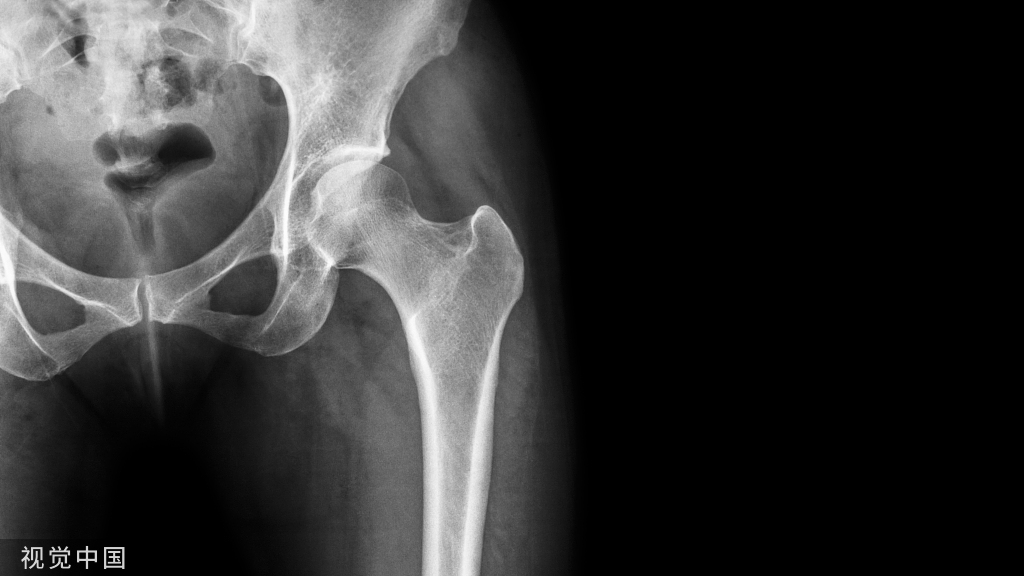

- 仅依赖肩关节正位X线片。肩关节正位X线片“灯泡征”及“肩胛盂空虚征”缺乏特异性,非诊断肩关节后脱位的可靠表现。肩关节X线腋位片及肩胛骨侧位片更加可靠。

应该说是一个典型的“灯泡征”影像,但是并未引起注意。

当地接诊医生应该说还是很负责的,同时拍了健侧片对比:

就诊我院后完善CT,诊断明确——左肩关节后脱位:

予以手法复位后拍片复查显示“灯泡征”消失,复位成功。讨论:肩关节后脱位在临床较为少见,特别是影像科经验不足很容易漏报,所以我们临床医生一定要自己仔细阅片,同时要结合体查来进行诊断,防止漏诊。肩关节后脱位时体查也有明显特征:肩关节前方明显变平,喙突较平时明显凸起容易触及,而肩关节后方明显丰满,上臂一般处于内旋内收位,无法主动外旋外展。肩关节后脱位的手法复位相对于前脱位的复位来说也比较容易。患者一般可以取坐位,助手自患侧腋下环抱患者稳定患者躯体,术者一手拉患肢上臂稍牵引内旋,一手自后方推顶肱骨头一般可以复位,如果单纯推顶无法复位也可以术者两手握住伤肢缓慢外展并沿肱骨纵轴牵引,然后逐渐外旋上臂即可复位。整复完成后可以把持患肢作肩关节各个方向的小幅度被动活动,防止肩关节粘连,肩关节后脱位的固定方法与肩关节前脱位的固定方法不同,应将患肢置于上臂外展、后伸、外旋位固定,即外展30度、后伸30度和轻度外旋位,用外展支架固定3周后,循序渐进开始肩关节功能康复。